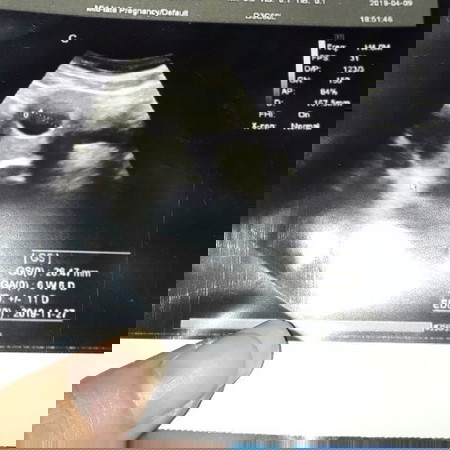

yg penting jaga pola makan n minum vitamin nya jgn lewat yah bund. kalo aku alhamdulillah 6week5day udah keliatan janinnya kecil bgt emng lewat usg perut. ukurannya masih 0,80cm. tp tiap bunda2 kondisinya berbeda. mudah2an 2minggu lg udah keliatan bund aamiin krna antara HPHT dgn usia kandungan di USG itu sering berbeda.